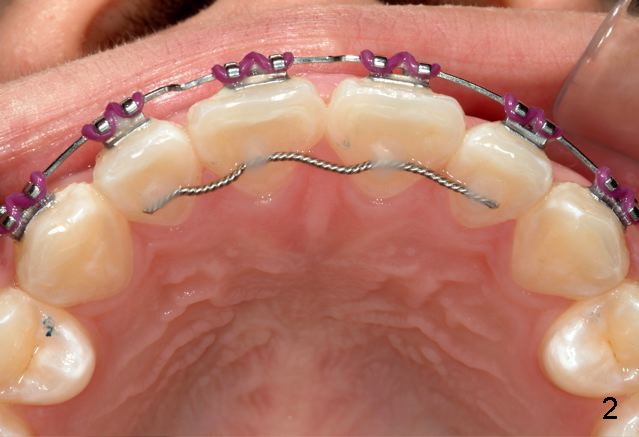

Answer: I was afraid tooth #8 would try to rotate (Fig.).  I do not like U bonded retainers as much as lower but I thought maybe in this case due to #8 initial position.  I have provided 2 removable retainers to fit over for insurance!

Excellent thinking.  According to the final photos, you must have done something to overcorrect the rotation of the two centrals.  Did you do it with purpose or by accident?  How did you do it, although Amy may not like it.  It seems to me that there is no practical way to overcorrect rotation.